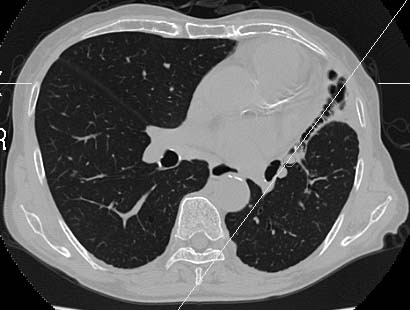

Data acquired & processed by R. Kato M.D.